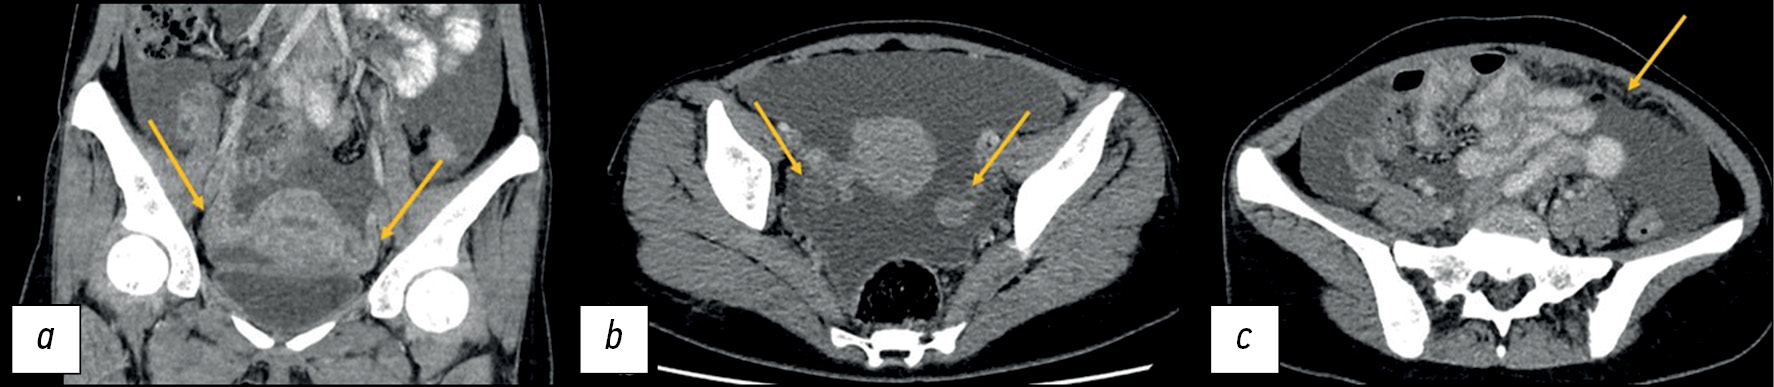

An abdominal CT with intravenous contrast was performed because of changes seen on previous examinations:

- A large amount of free liquid

- The mesentery and greater omentum were compressed and edematous, and lymph nodes up to 8 mm were visualized.

- The ovaries were not enlarged. They had an uneven contour and a heterogeneous structure (Figure 2).

Fig. 2. Computed tomography of the abdominal and pelvic organs with contrast enhancement: a - coronal plane; b, c — axial plane. The arrows indicate: a, b — ovaries with a heterogeneous structure and uneven contours; c — infiltration and swelling of the greater omentum.